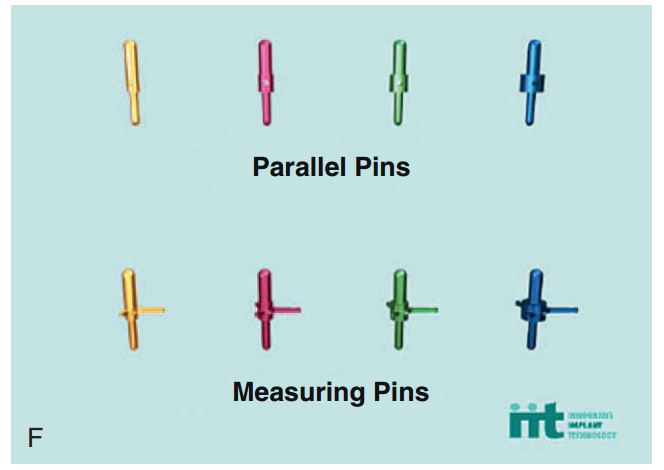

Giúp xác định đúng vị trí đặt Implant và lựa chọn đường kính Implant tối ưu nhất (H2.18). Bộ hướng dẫn ITT gồm có:

– Pin song song, để xác định độ song song của Implant.